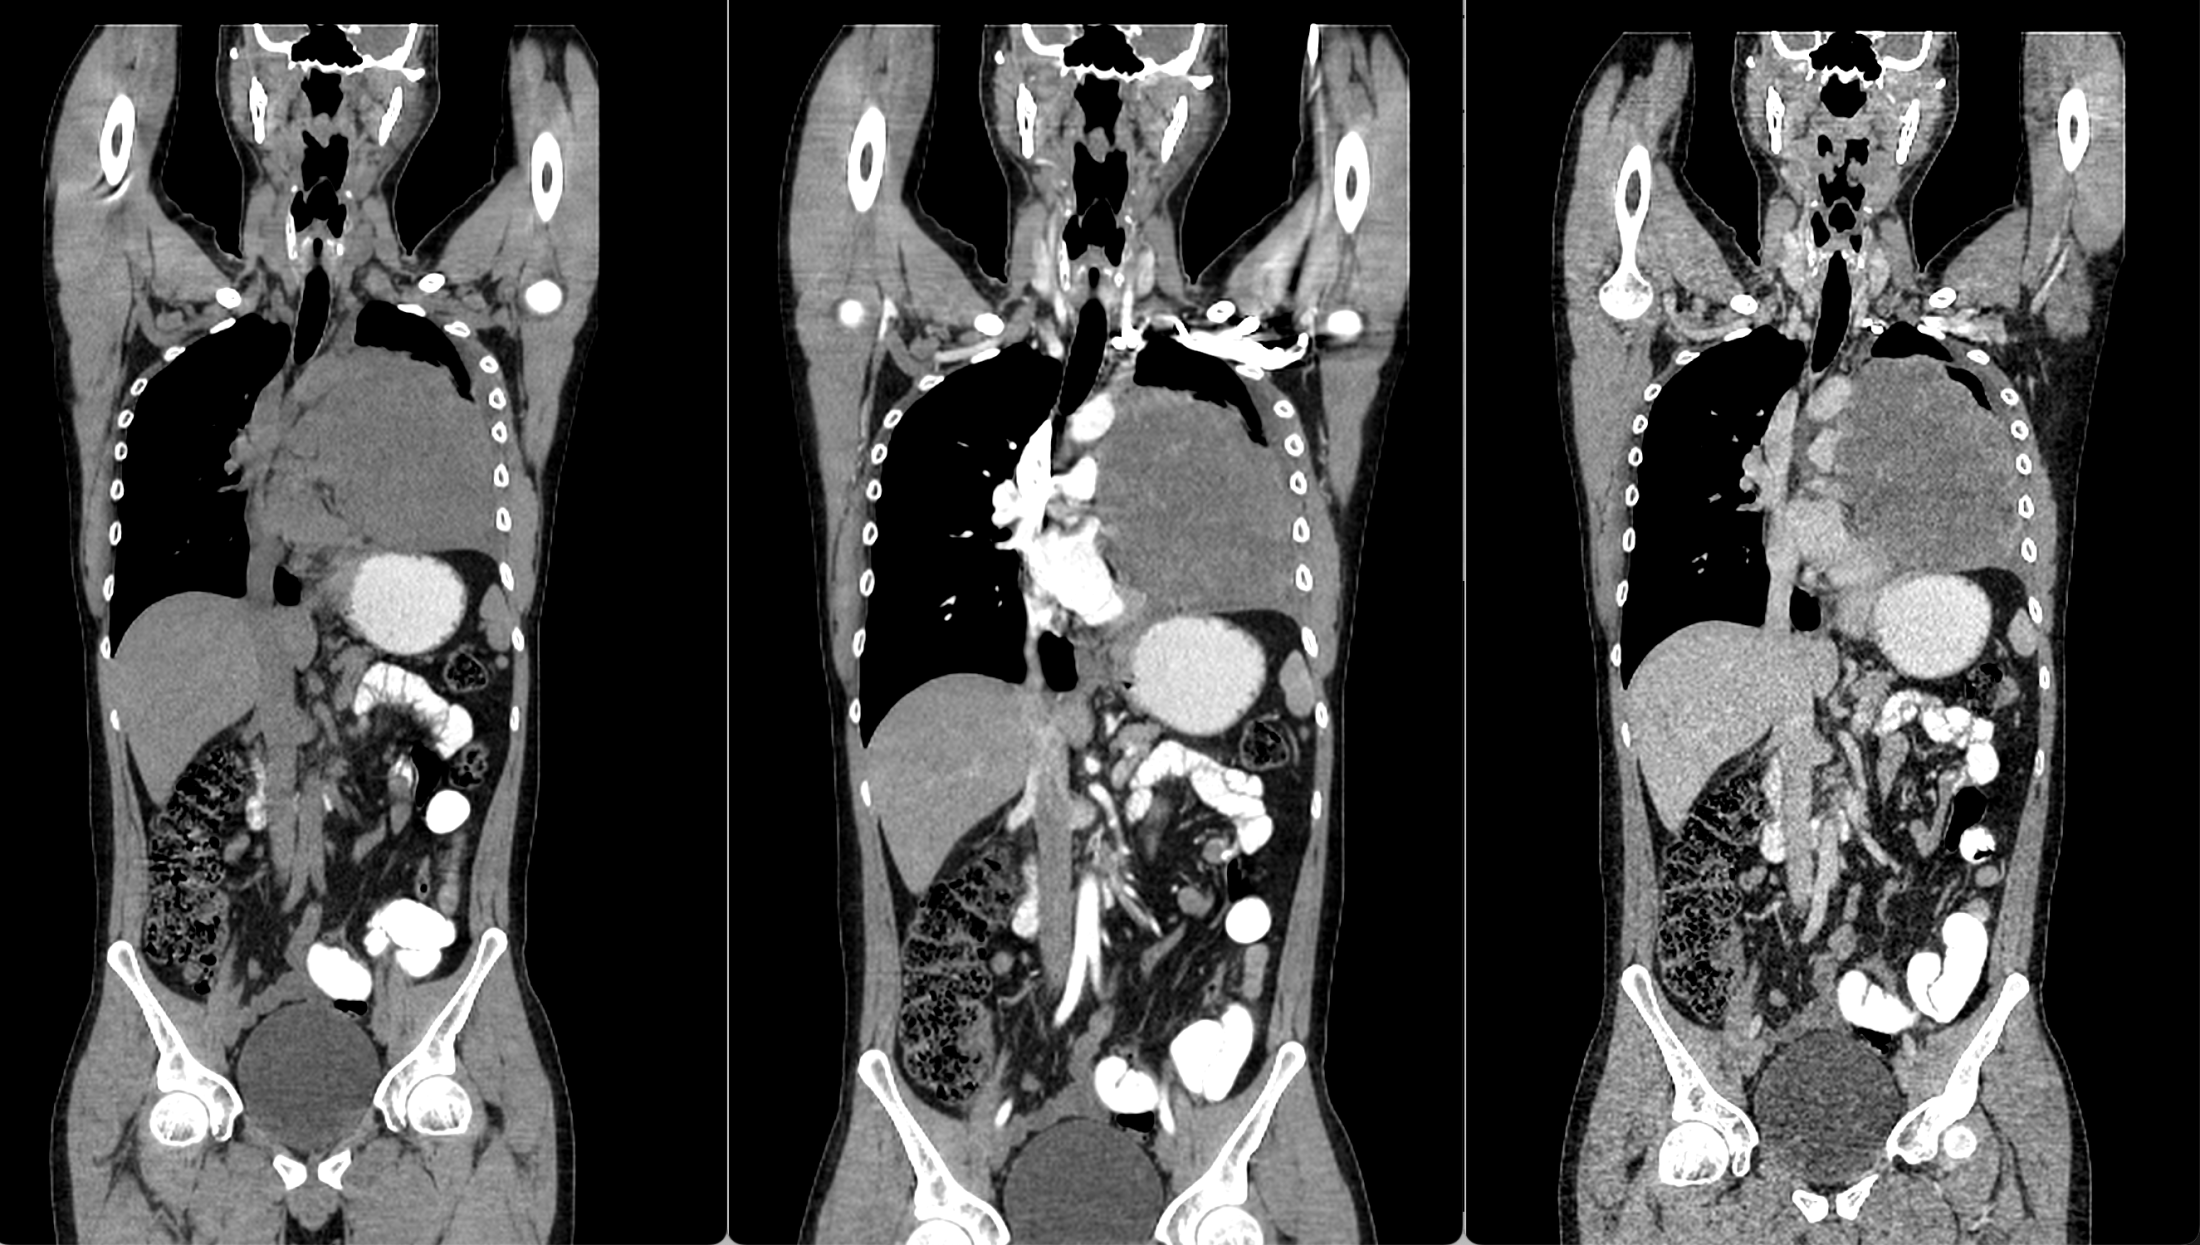

图4 冠状位成像显示肿块没有延伸到形成心脏轮廓的心脏边缘;存在胸腔积液。

后前位胸片显示左肺周围病变,伴有对侧气管移位和心缘剪影征阴性,同时由于对侧肺代偿性过度充气导致左半膈肌升高。侧面投影显示胸骨后间隙占位,并伴“脊柱征”。增强CT显示先前识别的病变表现不均匀性,主要呈现周边强化,以及中央低密度区域,可能表明有坏死。其位于前纵隔内,不浸润邻近组织,但支气管血管结构向对侧移位。此外,可以观察到右肺动脉受压,同时存在胸腔积液